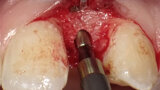

Aproximální rozšíření mezi kořeny zubů za účelem zavedení úzkého implantátu